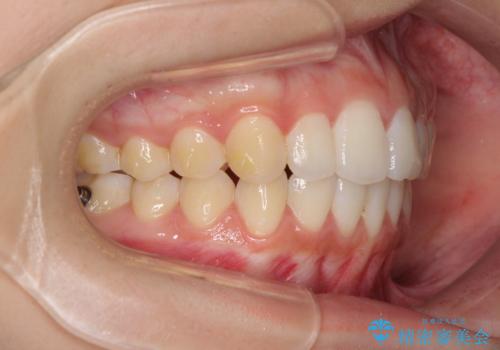

前歯のデコボコと突出感 インビザラインで改善

インビザラインによる上下歯列の側方拡大と後方移動、IPR(歯と歯の間を削る)にるスペースの獲得により歯列を整えることとしました。

骨格的な左右差があったため、上下の正中を合わせることは困難かと思われましたが、何とか合わせることができました。

一方、骨格の差は改善できないため、奥歯の咬み合わせに物足りなさを感じました。